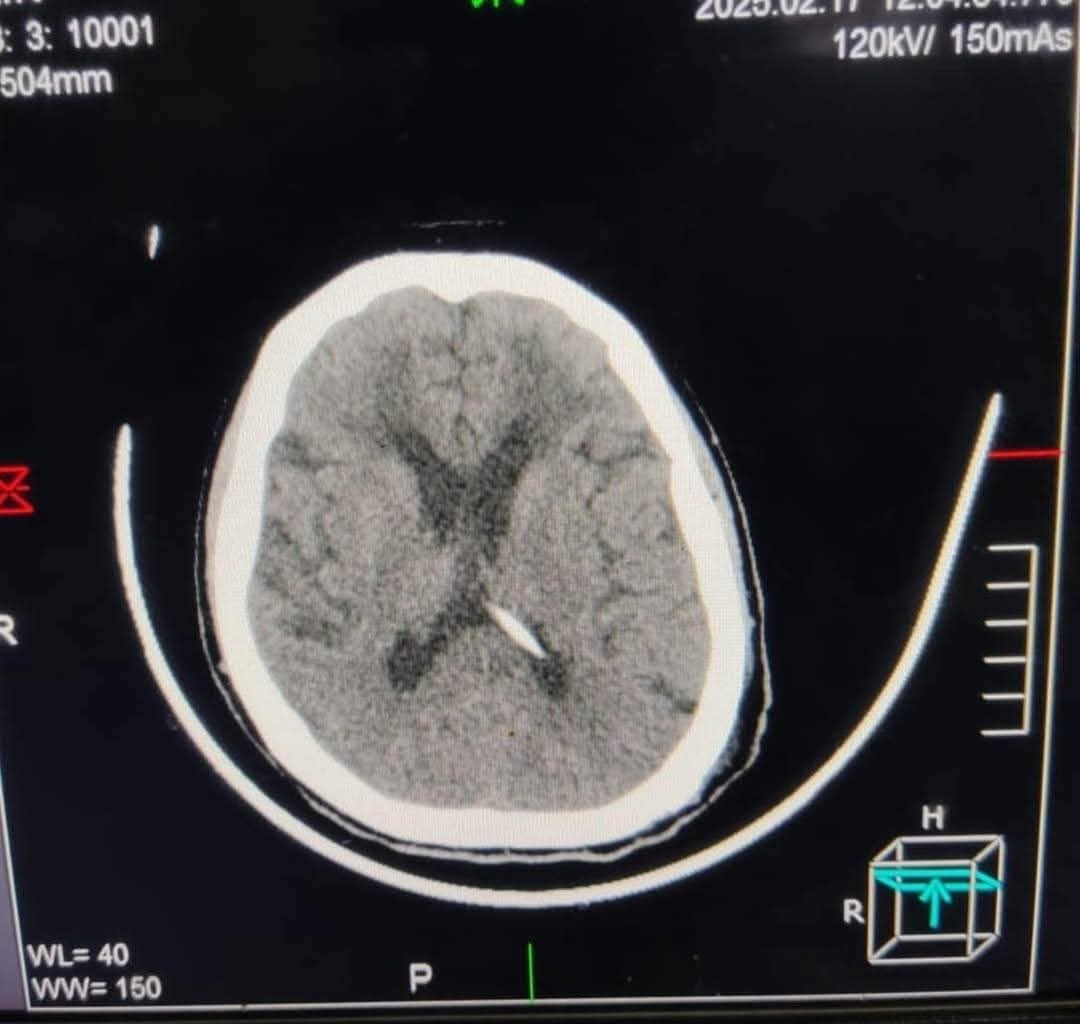

أجرى الفريق الطبى بمستشفى دمياط العام بقيادة الدكتور معاذ ياسر العبد جراحة دقيقة لتركيب صمام مخى بريتونى لمريضة تعانى من فشل كلوي وغيبوبة.

حيث تم إجراء الفحوصات اللازمة لها قبل إجراء الجراحة والتى تبين خلالها من وجود استسقاء حاد بالمخ أثر على درجة الوعى والحركة، وعليه تم التعاون مع كافة الأقسام للتجهيز لإجراء الجراحة وتركيب الصمام لصرف ضغط السائل النخاعى الزائد وخروج الحالة بدرجة وعى كاملة بعد نجاح العملية، والتى تُعد الأولى من نوعها بمستشفيات مديرية الصحة بدمياط، فى إطار الجهود المبذولة للقضاء على قوائم الانتظار بتخصص جراحات المخ والأعصاب